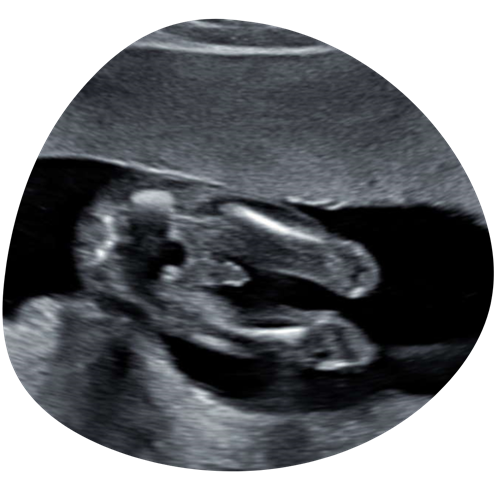

Geslachtsbepaling

Vanaf 15 weken zwangerschap kunnen we het geslacht van je kindje bepalen. Een volle blaas zorgt ervoor dat ze gaan liggen, hierdoor is het geslacht beter in beeld te brengen en krijgen we de mooiste echo beelden van je kindje

€35 (15 minuten)